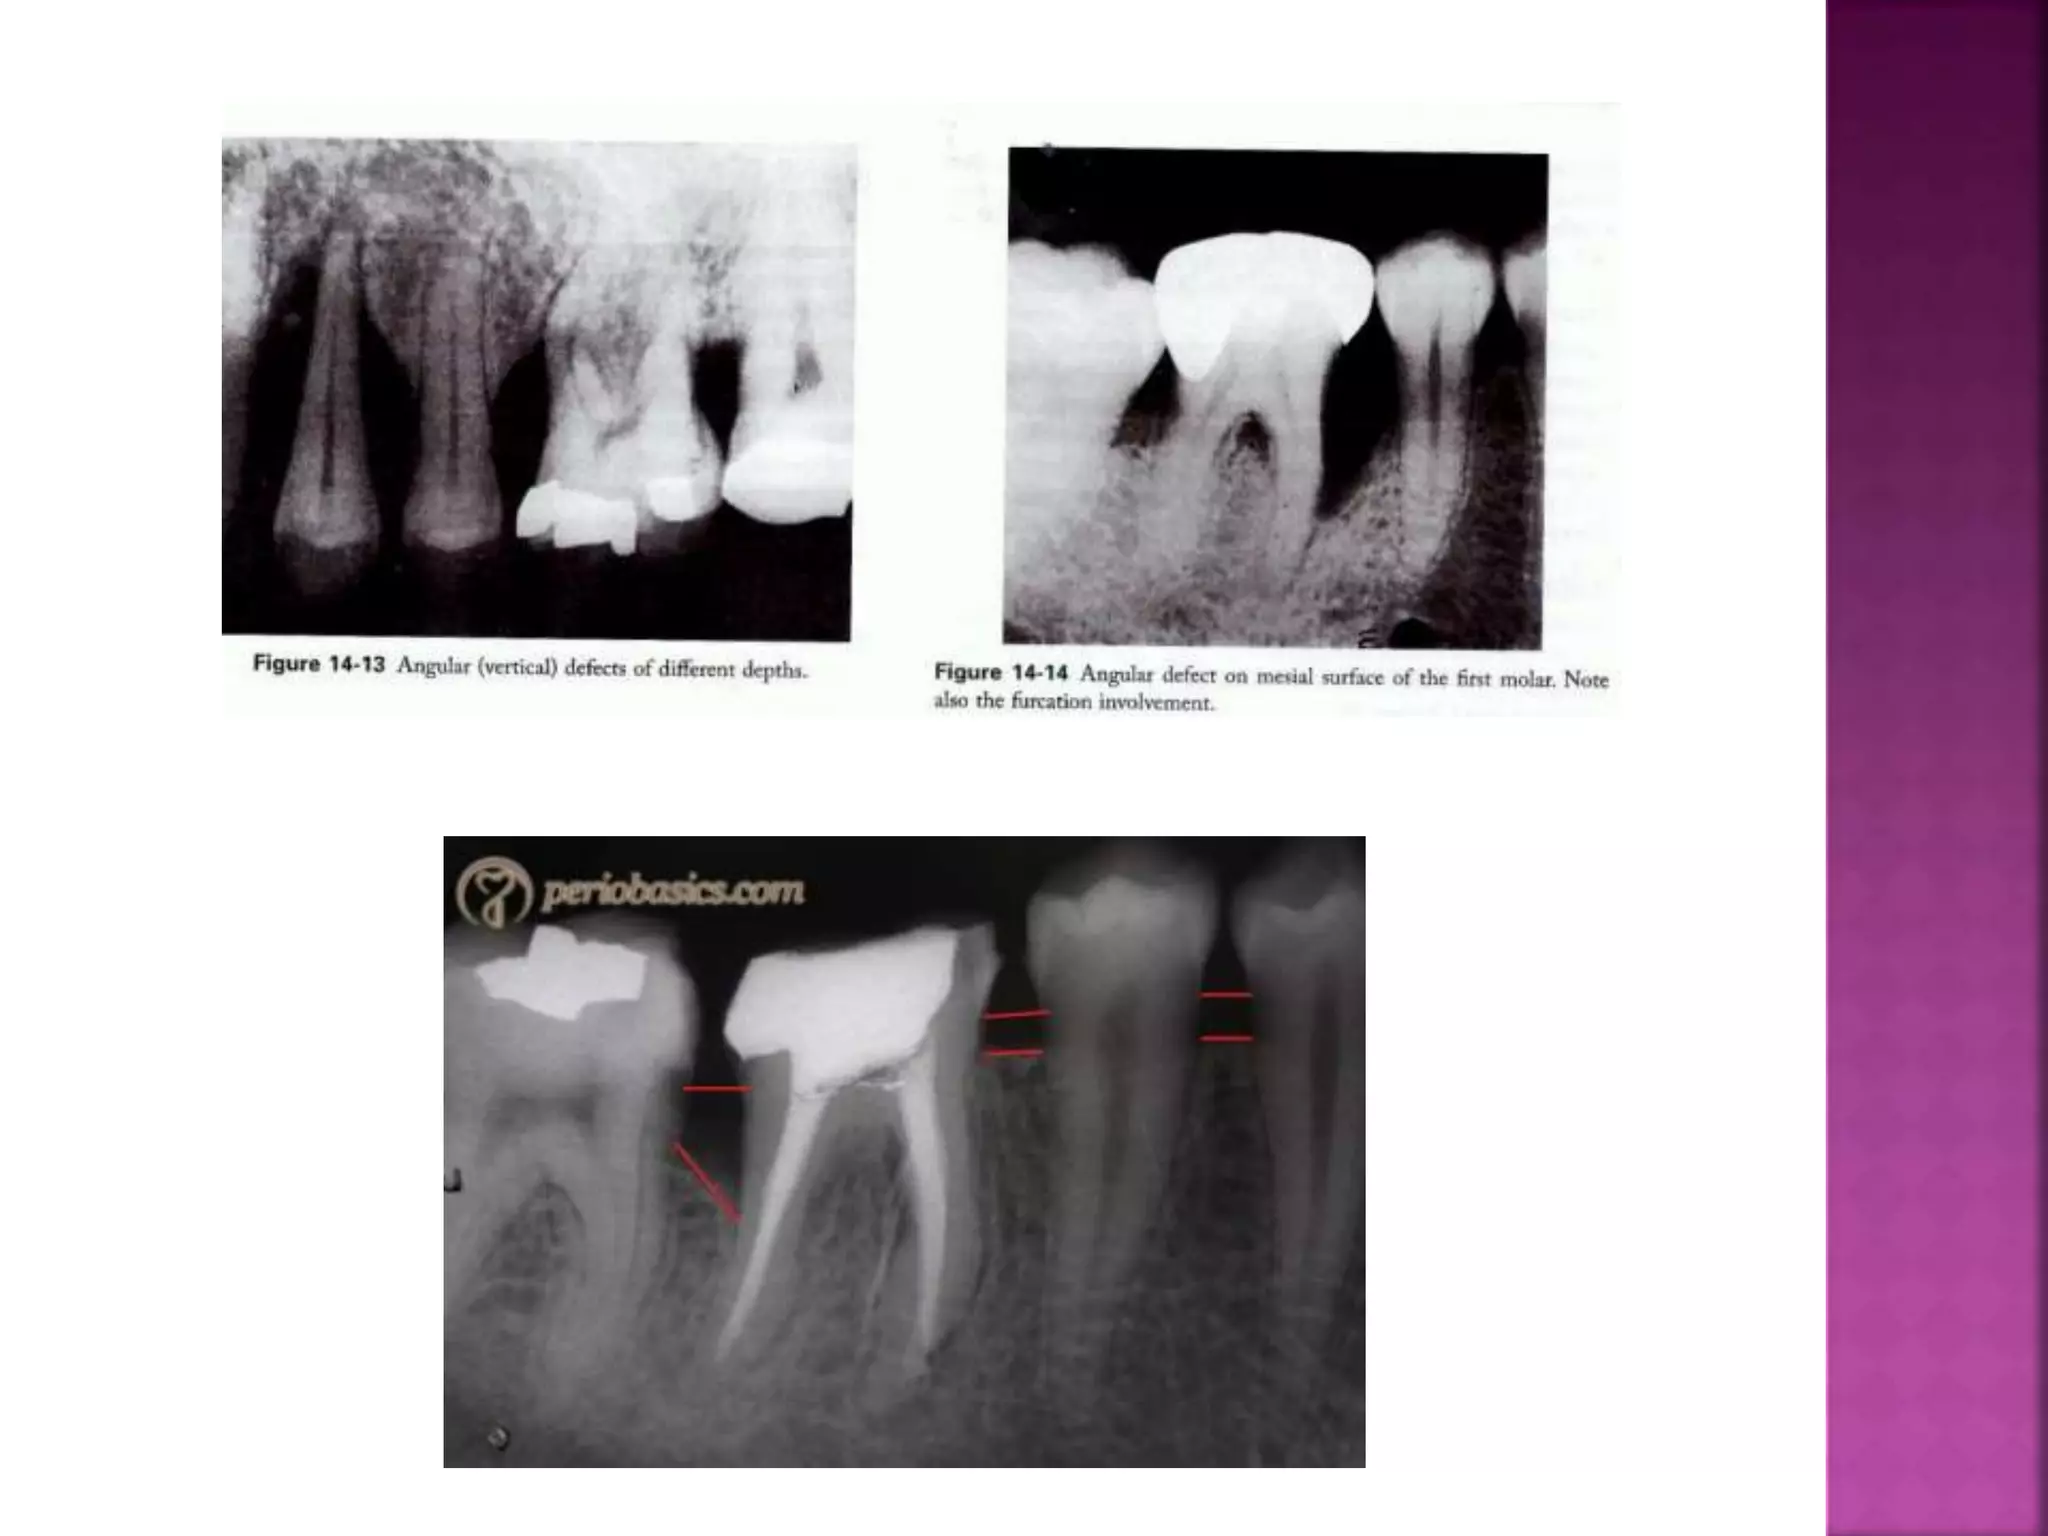

This document summarizes the classification of osseous defects caused by periodontal disease. It describes different types of horizontal bone loss including osseous craters and bulbous bony contours. It also discusses vertical/angular bone loss and classifications proposed by Glickman and Goldman/Cohen. Furcation involvement is classified using scales proposed by Glickman and Tarnow/Fletcher. Understanding the nature of these bone alterations is important for effective diagnosis and treatment planning.